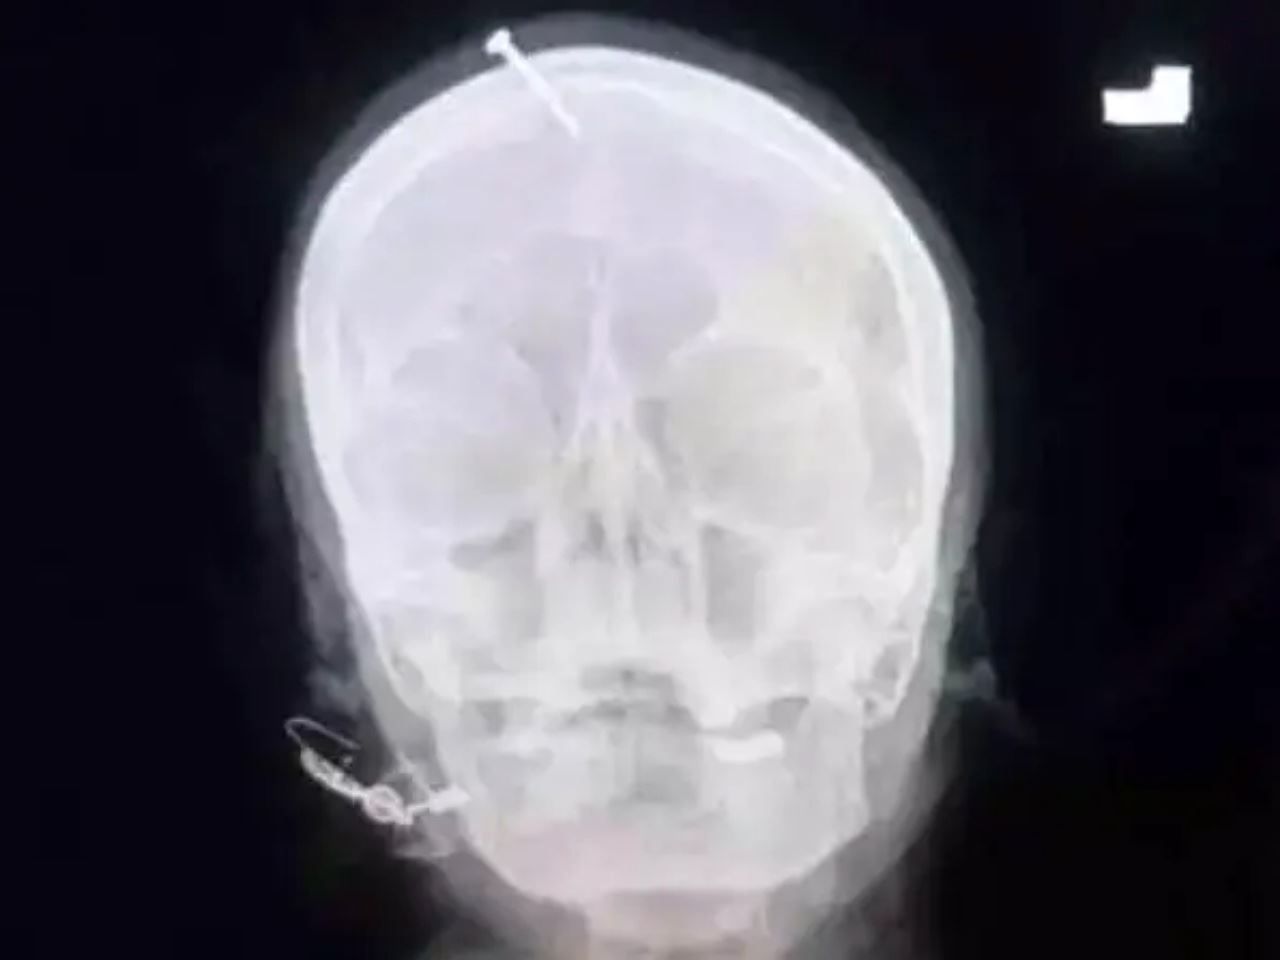

Imbasan X-ray menunjukkan paku itu terbenam dalam tengkorak kepalanya, namun mujur ia tidak mengenai bahagian otak.

“Kita dapati tukul atau objek berat digunakan bagi memasukkan paku ke dalam kepalanya.

“Dia masih sedar sepenuhnya tetapi dalam keadaan terlalu sakit,” katanya.